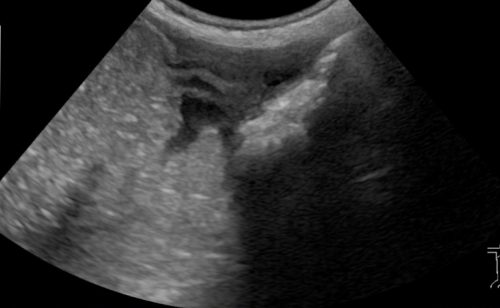

「気管虚脱の診断」特集スライド(末松正弘先生)

疾患特集スライド